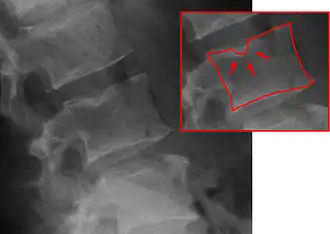

| X-ray image of Schmorl's nodes in the lumbar spine | |

Schmorl's nodes can be detected with X-rays, although they can be imaged better by CT or MRI. They are considered to be vertical disc herniations through the cartilaginous vertebral body endplates. Schmorl's nodes can sometimes be seen radiographically, however they are more often seen on MRI, even when not visible on plain X-rays. They may or may not be symptomatic, and their etiological significance for back pain is controversial. In a study in Spine by Hamanishi, et al., Schmorl's nodes were observed on MRI in 19% of 400 patients with back pain, and in only 9% of an asymptomatic control group. The authors concluded that Schmorl's nodes are areas of "vertical disc herniation" through areas of weakness in the endplate.[4]